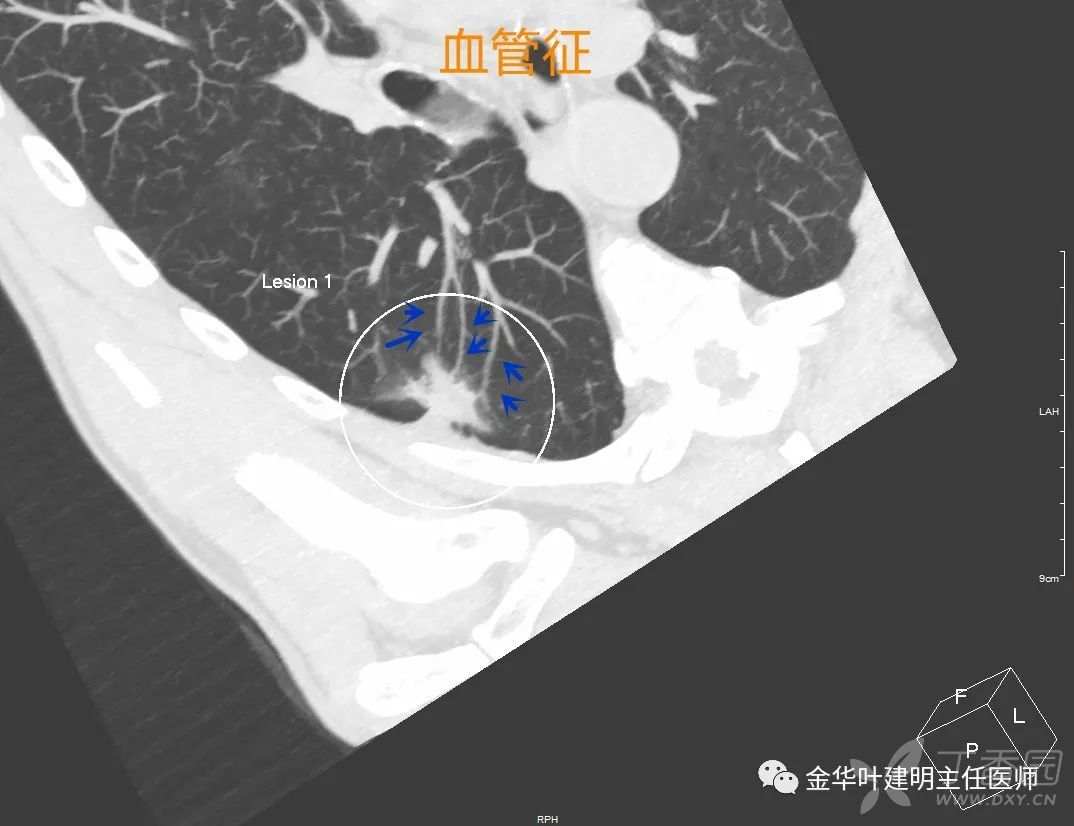

血管征

血管征:也叫血管集束征,直白说,就是有血管进入病灶里面去。若是单一血管进入,有时候像枝头上挂着个果实的样子。像上图这种,是多根血管均改变自然走行,趋向病灶,说明病灶对血供需求比较旺盛,也是恶性的征象之一。